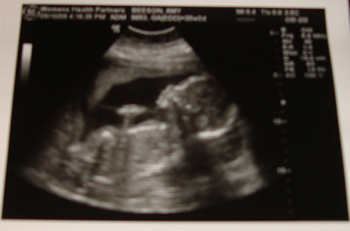

We're officially half way though the pregnancy, and we've had two Ultrasound sessions, and have not yet found out if it's a boy or a girl baby.

We have one more scheduled Ultrasound session...should we find out if it's a boy or a girl, or leave it up to be a surprise?